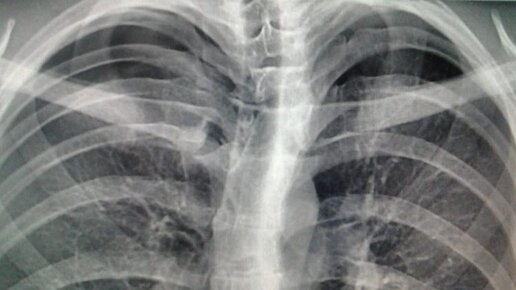

Апикальный пневмоторакс — что это такое?

Апикальный (расположенный в верхней части) пневмоторакс представляет собой нарушение движения воздуха в легком и чрезмерное его количество в плевральной зоне. Патология вызывает уменьшение всего или части легкого, его смещение, сдавление кровеносных сосудов, опущение диафрагмы, нарушение дыхания. Возникает нарушение движения воздушного потока, повышение давления в легких. Какова причина данной патологии? Факторами, провоцирующими данное явление, может выступать травматизация верхней части туловища,...